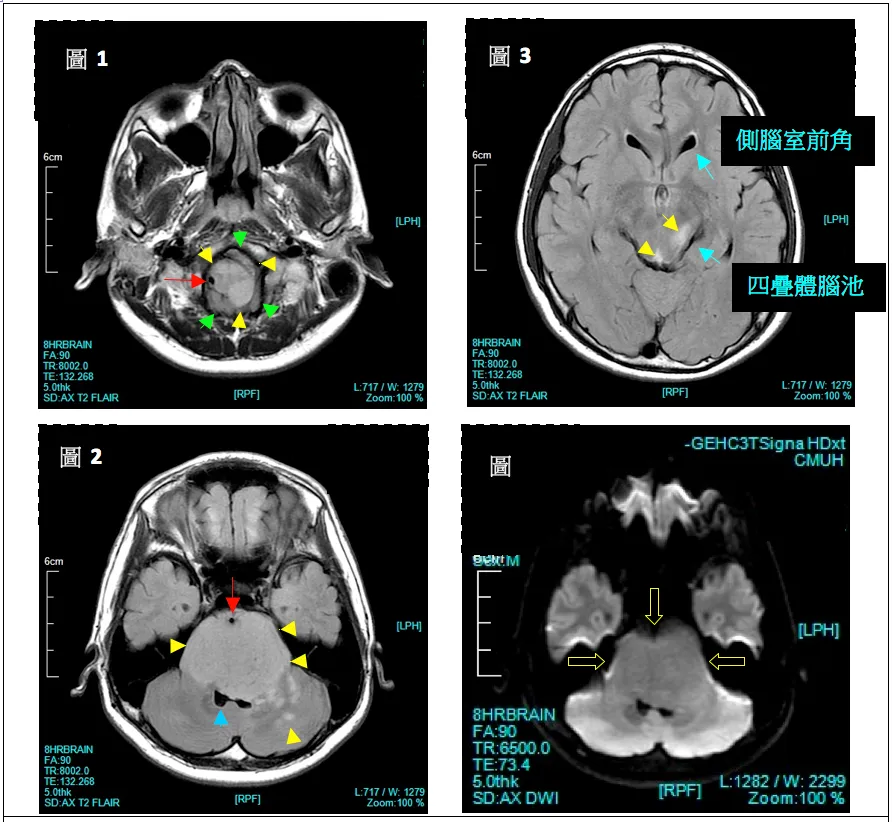

4、影像学MR解析

整个脑干(延髓、脑桥、中脑)在T2WI上都有信号增强的病灶(黄色箭头)。脑室系统虽被挤压变形,但未出现脑室扩大、水脑的情形(蓝色箭头)。肿瘤核心位于脑桥的中心,并且在出现时可以占据其轴向直径的50%以上,通常包绕基底动脉。虽然DIPG沿纤维束浸润性和弥漫性生长邻近的位置,但它们很少转移到远处。

Fig.1:中病灶将脑桥撑大,怀疑往外长出小的外凸物(绿色箭头)。病灶紧邻右椎动脉(红色箭头)。

Fig.2:显示整个脑桥中充满高信号灶,脑桥体积变大,但形状大致不变。基底动脉被肿瘤包围且被往前推(红色箭头),第四脑室被挤压,左边尤甚(蓝色箭头),肿瘤扩散至小脑。

Fig.3:显示中脑也见到增强的讯号。